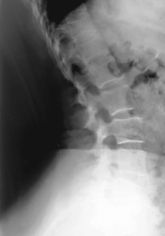

• Erect (sitting or standing) in lateral position, C spine aligned and centered to CR (and centerline of IR)

• Top of IR ≈1-2″ (3-5 cm) above level of EAM

• Raise chin slightly (to remove mandible angles from spine).

• Relax and depress both shoulders evenly (weights in each hand may be necessary to visualize C7).